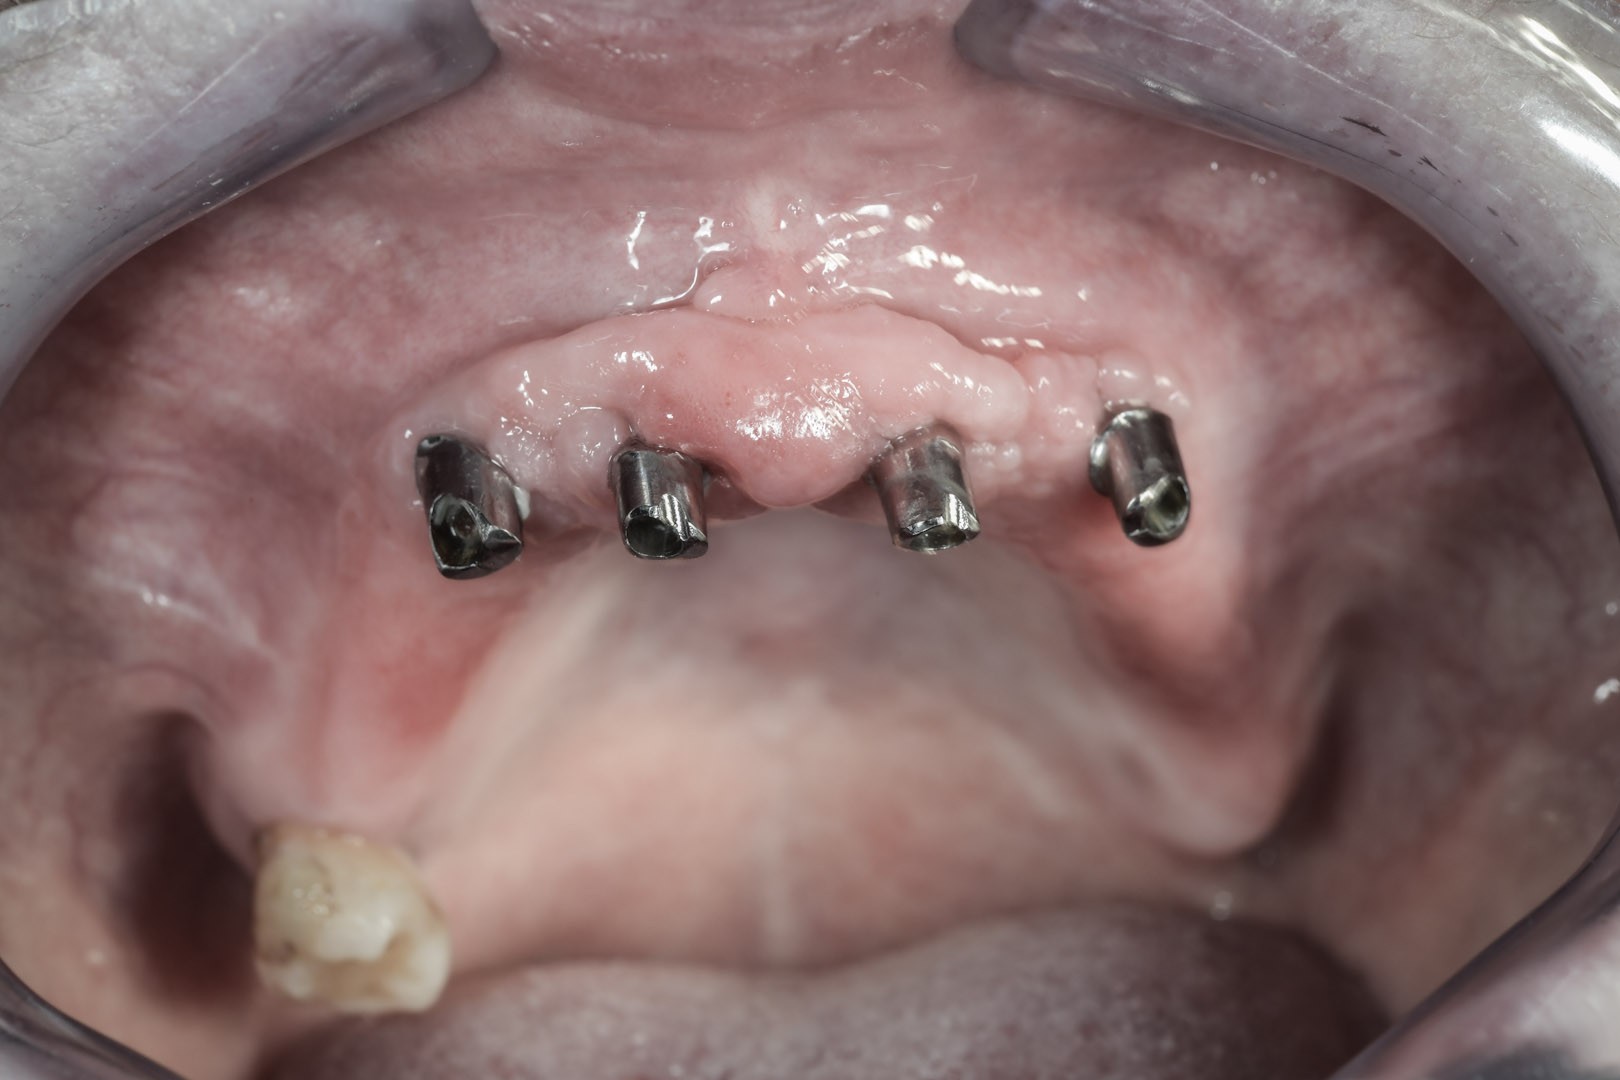

Zazwyczaj umocowuje je do podłoża od 2 do 4 wszczepionych implantów, dla których optymalną pozycją jest przednia część wyrostka zębodołowego szczęk lub żuchwy.

ALL-ON-4

• Stwarza możliwość wykonania całkowitej rekonstrukcji uzębienia tylko na 4 implantach.

• Pozwala na uniknięcie obciążających zabiegów rekonstrukcji kostnej.

• Poprzez użycie pochylonych implantów w odcinkach bocznych pozwala uniknąć uszkodzenia ważnych szczegółów anatomii oraz zwiększa powierzchnię przylegania i osteointegracji implantów z kością.

• System umożliwia natychmiastowe obciążenie implantów tymczasowym mostem protetycznym zaraz po założeniu implantów.

• Możliwe jest zastosowanie systemu nawigacji komputerowej NobelGuide, celem precyzyjnego zaplanowania pozycji implantów jeszcze przed zabiegiem chirurgicznym. Dzięki użyciu specjalnych szablonów chirurgicznych możliwa jest implantacja w optymalnych pozycjach, które uwzględniają budowę i niedostatki kości.

Jest to opatentowana metoda rekonstrukcji implanto-protetycznej kompletnego uzębienia stosowana przy bezzębiu zarówno dla dolnego, jak i górnego łuku zębowego. Bazuje na charakterystycznie wszczepionych 4 implantach zębowych, stąd nazwa Wszystko na 4. Dwa środkowe wprowadzane są w kość prostopadle do jej brzegu i równolegle do siebie, dwa boczne wszczepiane są pod kątem 45 stopni. Rozwiązanie protetyczne to most przykręcany na stałe do implantów, który może być zakładany natychmiast po zabiegu implantacji lub w czasie odroczonym. Gwarancją natychmiastowego przywrócenia funkcji żucia jest odpowiednia siła osadzania implantów mierzona dynamometrycznie w trakcie ich wszczepiania oraz należyta staranność wykonania i osadzenia prac protetycznych.